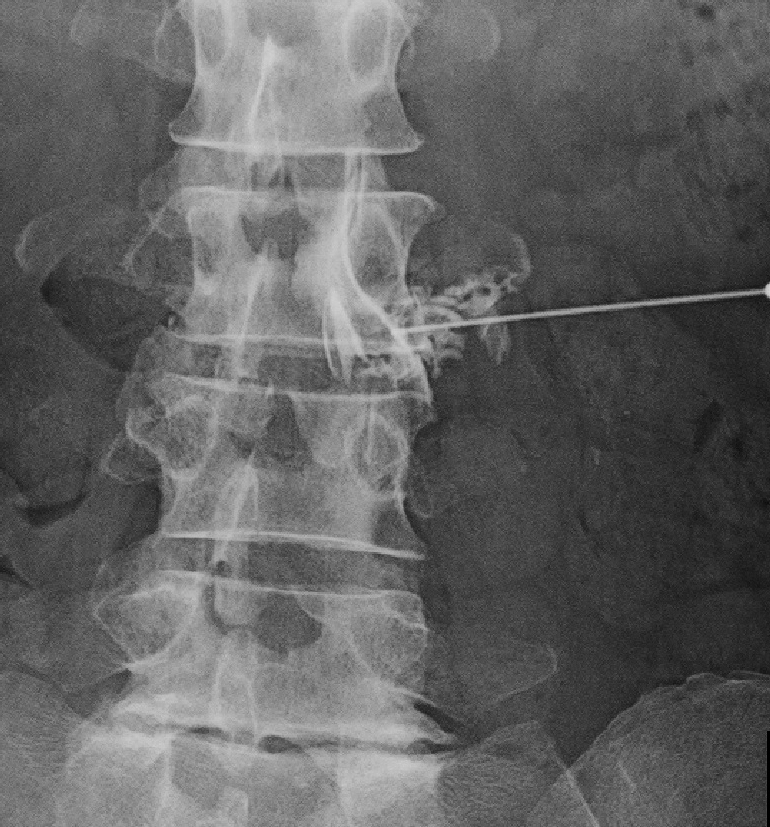

腰椎MRI画像

腰のMRI検査では、軽度ですがL23に椎間板ヘルニアが確認され、右優位であり、これがこの患者さんの右膝痛の原因と判断しました。

現状では膝に病因となる所見がないので、私は膝への注射の治療はしませんと伝え、腰へのブロック治療を提案しました。患者さんはしぶしぶ同意され、7月31日に施行しました。

L3神経根ブロック像

すると、1週後には「けっこう痛い」というレベルの右膝痛は、「わずかに痛い」となり、患者さんはとても満足されることになりました。